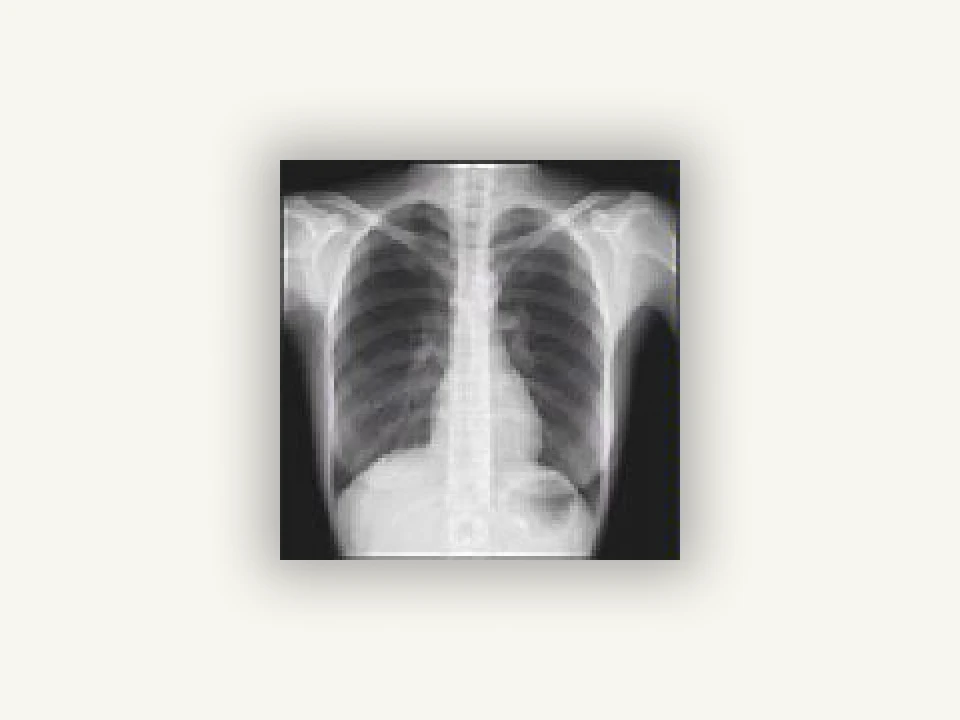

レントゲン

「レントゲン」とは?

エックス線は人体を通り抜けますが、骨などのように通りにくい所があるため、通り抜けたエックス線を写すと濃淡ができ体内の様子を知ることができます。肺や心臓、肺の間にある縦隔などの器官の病気について、様々な情報を得ることができますので、幅広く行なわれています。放射線の被曝があるため妊娠中のかたは検査をうけることができません。

何がわかる?

心臓や肺の病気の診断に有用です。心臓病など、心臓が拡大する病気が見つかるきっかけにもなります。また、心不全が悪くなり肺に水が貯まるのもわかります。また肺がん、肺結核、肺炎などでは、異常が白い影として映りますし、COPDなど肺の病気では黒い影として写るので、肺の病気の早期診断に有用です。

検査方法

エックス線専用の検査室で、撮影するだけです。最新式のデジタル解析を行いますので現像時間がなくすばやく結果が出、検査後すぐに分かりやすいく丁寧に説明をします。